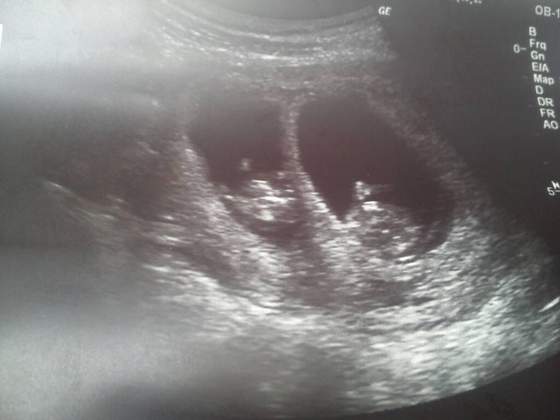

Ale po kolei. We wtorek byłam na badaniach prenatalnych. Obywatel Fikalski najpierw się wypiął pupą na świat i można go było zmierzyć i oblukać kręgosłup (cały), potem profilem i okazało się, że ma kość nosową w komplecie (jak miło) a potem jeszcze brzuszkiem do góry i dało się policzyć rączki, nóżki, żołądki itp, wszystko liczby całkowite dodatnie